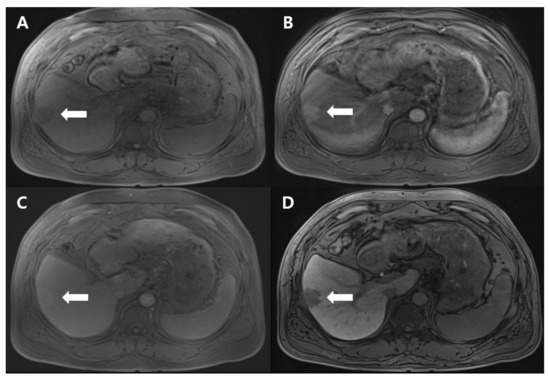

Histological examination of the resected mass revealed the loss of focal hepatocytes with increased capillary-sized vessels and fibrotic tissue in the cirrhotic liver, consistent with findings of parenchymal extinction (Figure 2). Some blood vessels in the lesion were partially occluded by intimal thickening. To exclude the presence of HCC, immunohistochemical staining was performed. The hepatocyte lobules in the lesion were negative for glypican-3, which is a diagnostic marker for HCC.

Figure 2. (A) Gross finding of the tumor. Grossly, an approximately 3-cm-sized, bright yellow mass-like lesion revealing ill-defined margins in the cirrhotic liver (white arrow); (B,C) Microscopic findings reveal focal loss of hepatocytes with increased capillary-sized vessel dilatation (B,C: hematoxylin and eosin staining, ×40, ×100, respectively); (D) Abundant fibrous septa with dilated capillary vessels are seen. (D: Trichrome staining ×40).